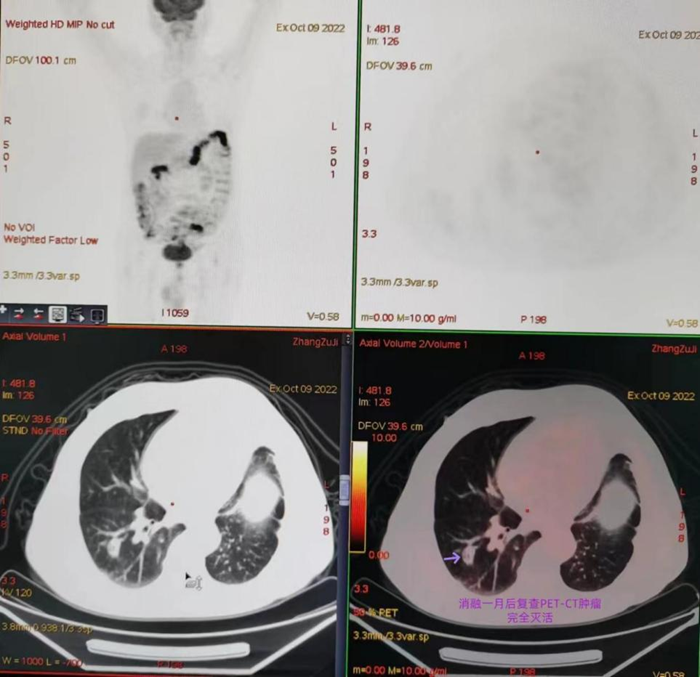

经了解,曾麟团队有丰富的经皮穿刺活检经验,至今已成功进行上千例各种高难度穿刺活检,故张先生慕名来我院就诊,经过仔细阅片及团队多次讨论后,曾麟在CT引导下行经皮穿刺,在毫厘之间避开数根肺内血管,一针到位,成功取到病理组织,最终病理结果证实是肺腺癌。根据患者病情为其采用经皮微波消融术,该手术创伤小,时间短,手术前后不到20分钟,张先生当晚即可下地行走,术后5天出院。在术后一个月复查时,PET-CT显示整个术区肿瘤活性完全消除,达到局部根治的效果,张先生和他的家属非常满意。